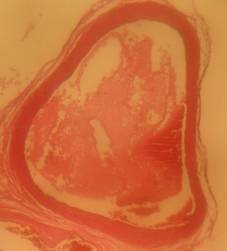

Histopathology

All rats were sacrificed, and their aortas were isolated for histological preparation. The aorta samples were fixed in 10% formaldehyde solution, and their slides were prepared. The slide preparations (6-8 µm thickness) were stained with hematoxylin/eosin. Each slide was scored based on the aorta conditions. The scores ranged from 0–4 with the following criteria: 0 normal condition; 1 if elastic fibres thickening was found; 2 if elastic fibres fragmentation, some foam cells, and fibrosis were found; 3 if smooth muscle proliferation was found, and 4 if plaque ulceration or plaque lipid calcification was found [10].

Morphological structure of aorta’s rats

Aorta’ slide was made every week for one month. Each group of the rats was killed, and the aorta’s rat was observed. From the morphological structure of aorta’s rat, atherosclerosis was scored as follows: on 4 point: 0, normal; 1, widening of elastic fibers with few foam cells; 2, fragmentation of elastic lamellae with numerous foam cells and fibrosis; 3, smooth muscle cells proliferation, medial lipid infiltration and fibrosis; 4, lipid-calcic plaque or ulcerated plaque [10].

The rats (n=4) from each group were sacrificed every week to observe the morphological structure of the aortas. From the lesions, it showed that AND could help chance severity aortic atherosclerosis. The score varied from group A1 until group A4. The aorta morphology of group A1 showed that one aorta had a widening of elastic fibers with few foam cells (score 1) and three aortas had the proliferation of smooth muscle cells (score 3) (fig. 5 A1). AND administration for four weeks could repair aorta condition. Group A4’ aorta morphology showed that three aortas became normal (score 0) and one aorta still had a widening of the first interlamellar (score 1) (fig. 5 A4). Atorvastatin administration could also help changing the severity of aortic atherosclerosis. The score also varied from group B1 until group B4. The aorta morphology of group B1 showed that one aorta had a widening of elastic fibers with few foam cells (score 1), two aortas had fragmentation of elastic lamellae with numerous foam cells and fibrosis (score 2), and one aorta had the proliferation of smooth muscle cells (score 3) (fig. 5 B1). Atorvastatin administration for four weeks could improve aorta condition. Group B4’ aorta morphology showed that two aortas became normal (score 0) and two aortas still had a widening of the first interlamellar (score 1) (fig. 5 B4). Contrarily, the morphological structure of atherogenic rats was getting worse week by week.

Fig. 5: Morphological structure of aorta in albino Wistar male rats 40x. A1, A2, A3, A4 is morphological structure of aorta’s AND rats fed atherogenic diet for 2 mo and continuing with AND for 1 w, 2 w, 3 w and 4 w; B1, B2, B3, B4 is morphological structure of aorta’s atorvastatin rats fed atherogenic diet for 2 mo and continuing with atorvastatin for 1 w, 2 w, 3 w and 4 w; C1, C2, C3, C4 is morphological structure of aorta’s rats fed atherogenic diet for 9th week, 10th week, 11th week, 12th week; D1, D2, D3, D4 is morphological structure of aorta’s rats fed regular diet for 9th week, 10th week, 11th week, 12th week. Black circle (O) = score 1; green circle (O) = score 2; red circle (O) = score 3; blue circle (O) = score 4